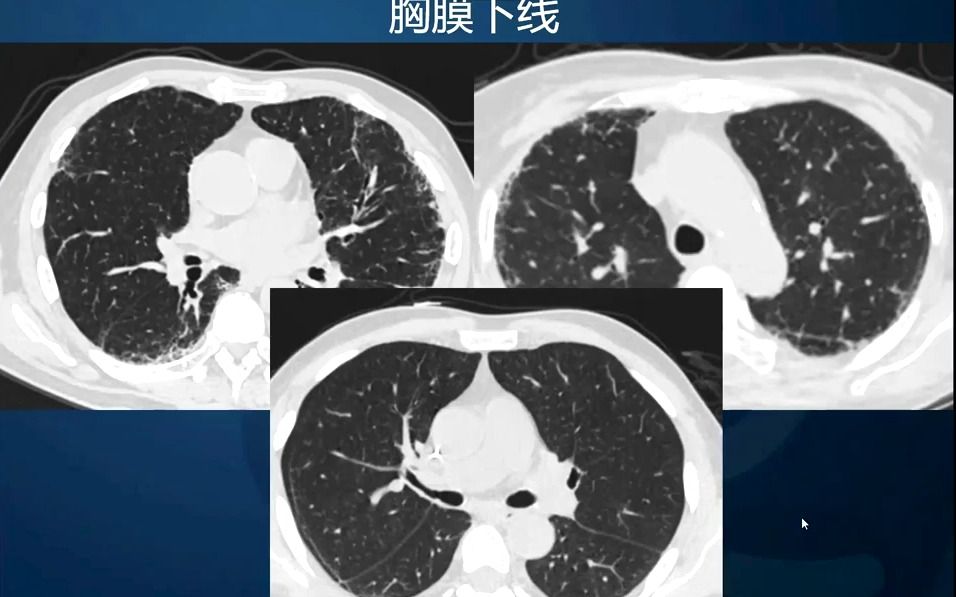

7.肺弥漫性病变的X线、CT影像分析-基础影像诊断培训系列